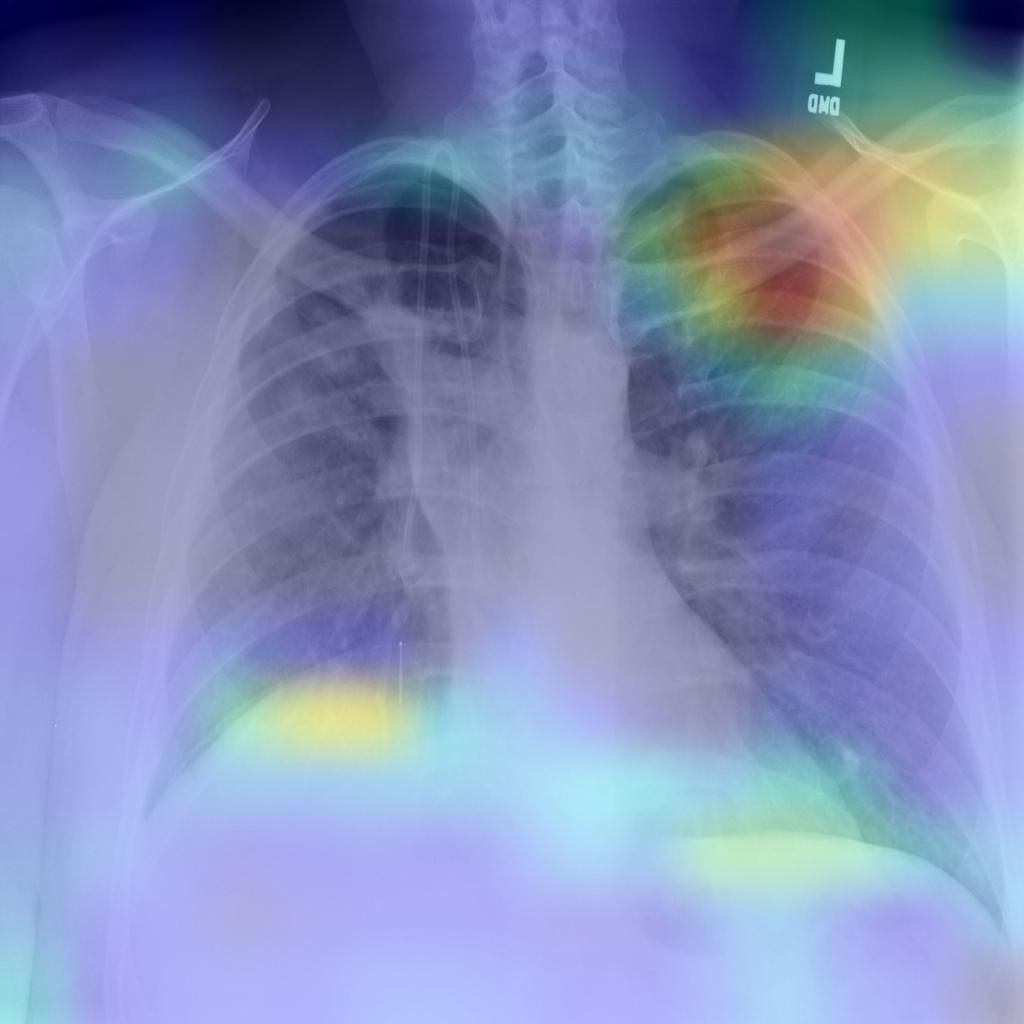

In our evaluation, we applied the Grad-CAM visual interpretation method to visually depict the salient areas where ECOVNet emphasizes the classification decision for a given chest X-ray image. Accurate and definitive salient region detection is crucial for the analysis of classification decisions as well as for assuring the trustworthiness of the results. In order to locate the salient area, the feature weights with various illuminations related to feature importance are used to create a two-dimensional heat map and superimpose it on a given input image. Figure 9 shows the visualization results of locating Grad-CAM using ECOVNet for each model snapshots. This salient area locates the area of each category area in the lung that has been identified when a given image is classified as COVID-19 or normal or pneumonia. As shown in Figure 9, for COVID-19, a ground-glass opacity(GGO) occurs along with some consolidation, thereby partially covering the markings of the lungs. Hence, it leads to lung inflammation in both the upper and lower zones of the lung. When examining the heat maps generated from the COVID-19 chest X-ray, it can be distinguished that the heat maps created from snapshot 2 and snapshot 3 points to the salient area (such as GGO). However, in the case of the normal chest X-ray, no lung inflammation is observed, so there is no significant area, thereby easily distinguishable from other classes, i.e., COVID-19 and pneumonia. As well, it can be observed from the chest X-ray for pneumonia is that there are GGOs in the middle and lower parts of the lungs. The heat maps generated for the pneumonia chest X-ray are localized in the salient regions with GGO, but for the 4th snapshot model, it appears to fail to identify the salient regions as the heat map highlights outside the lung. Accordingly, we believe that the proposed ECOVNet provides sufficient information about the inherent causes of the COVID-19 disease through an intuitive heat map, and this type of heat map can help AI-based systems interpret the classification results achieved from the proposed architecture.

Refer to captionRefer to captionRefer to captionRefer to captionRefer to captionRefer to captionRefer to captionRefer to captionRefer to captionRefer to captionRefer to captionRefer to captionRefer to captionRefer to captionRefer to captionRefer to captionRefer to captionRefer to captioni=1𝑖1i=1i=2𝑖2i=2i=3𝑖3i=3i=4𝑖4i=4i=5𝑖5i=5COVID-19Normal Pneumonia Grad-CAM Visualization for ith Snapshot Model

Figure 9: Grad-CAM visualization for the proposed ECOVNet considering the base model EfficientNet-B5. A total of 5 (five) model snapshots were generated during the training process.